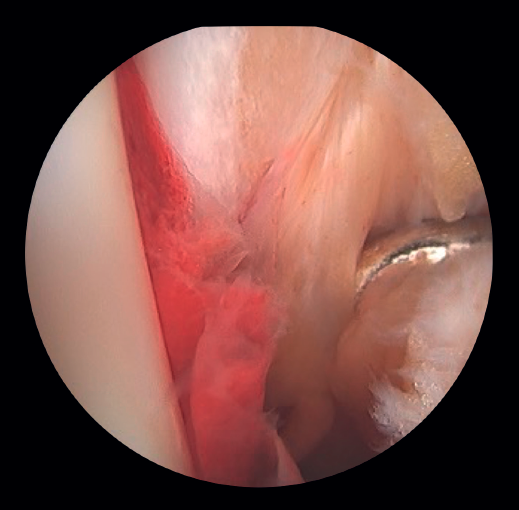

Si la lesión del deltoideo compromete solo a la parte anterior, podremos realizar la reinserción de forma artroscópica mediante implantes reabsorbibles. Si la desinserción del deltoideo es completa, preferimos realizar la reinserción de forma abierta por la dificultad que entraña colocar los implantes en la zona posterior del maléolo y el riesgo de lesión neurovascular (Figura 5).

- Evaluación del ligamento deltoideo: la rotura del ligamento deltoideo puede causar inestabilidad medial persistente tras la reducción del peroné, asociándose a dolor, disfunción y riesgo de OAPT si no se trata adecuadamente. Su reparación en fracturas agudas del tobillo ha demostrado mejorar la reducción del espacio claro medial (ECM), los resultados funcionales (AOFAS) y reducir las complicaciones postoperatorias. En fracturas de tipo SER, la evaluación de la estabilidad medial es clave: mientras que en las fracturas de tipo SER II el fascículo profundo del ligamento deltoideo suele estar preservado, en las fracturas de tipo SER IV hay lesión medial completa que compromete la mortaja tibioperonea y requiere tratamiento quirúrgico(19).

En las fracturas con lesión del ligamento deltoideo se ha detectado un aumento de las lesiones intraarticulares, como lesiones osteocondrales(19).